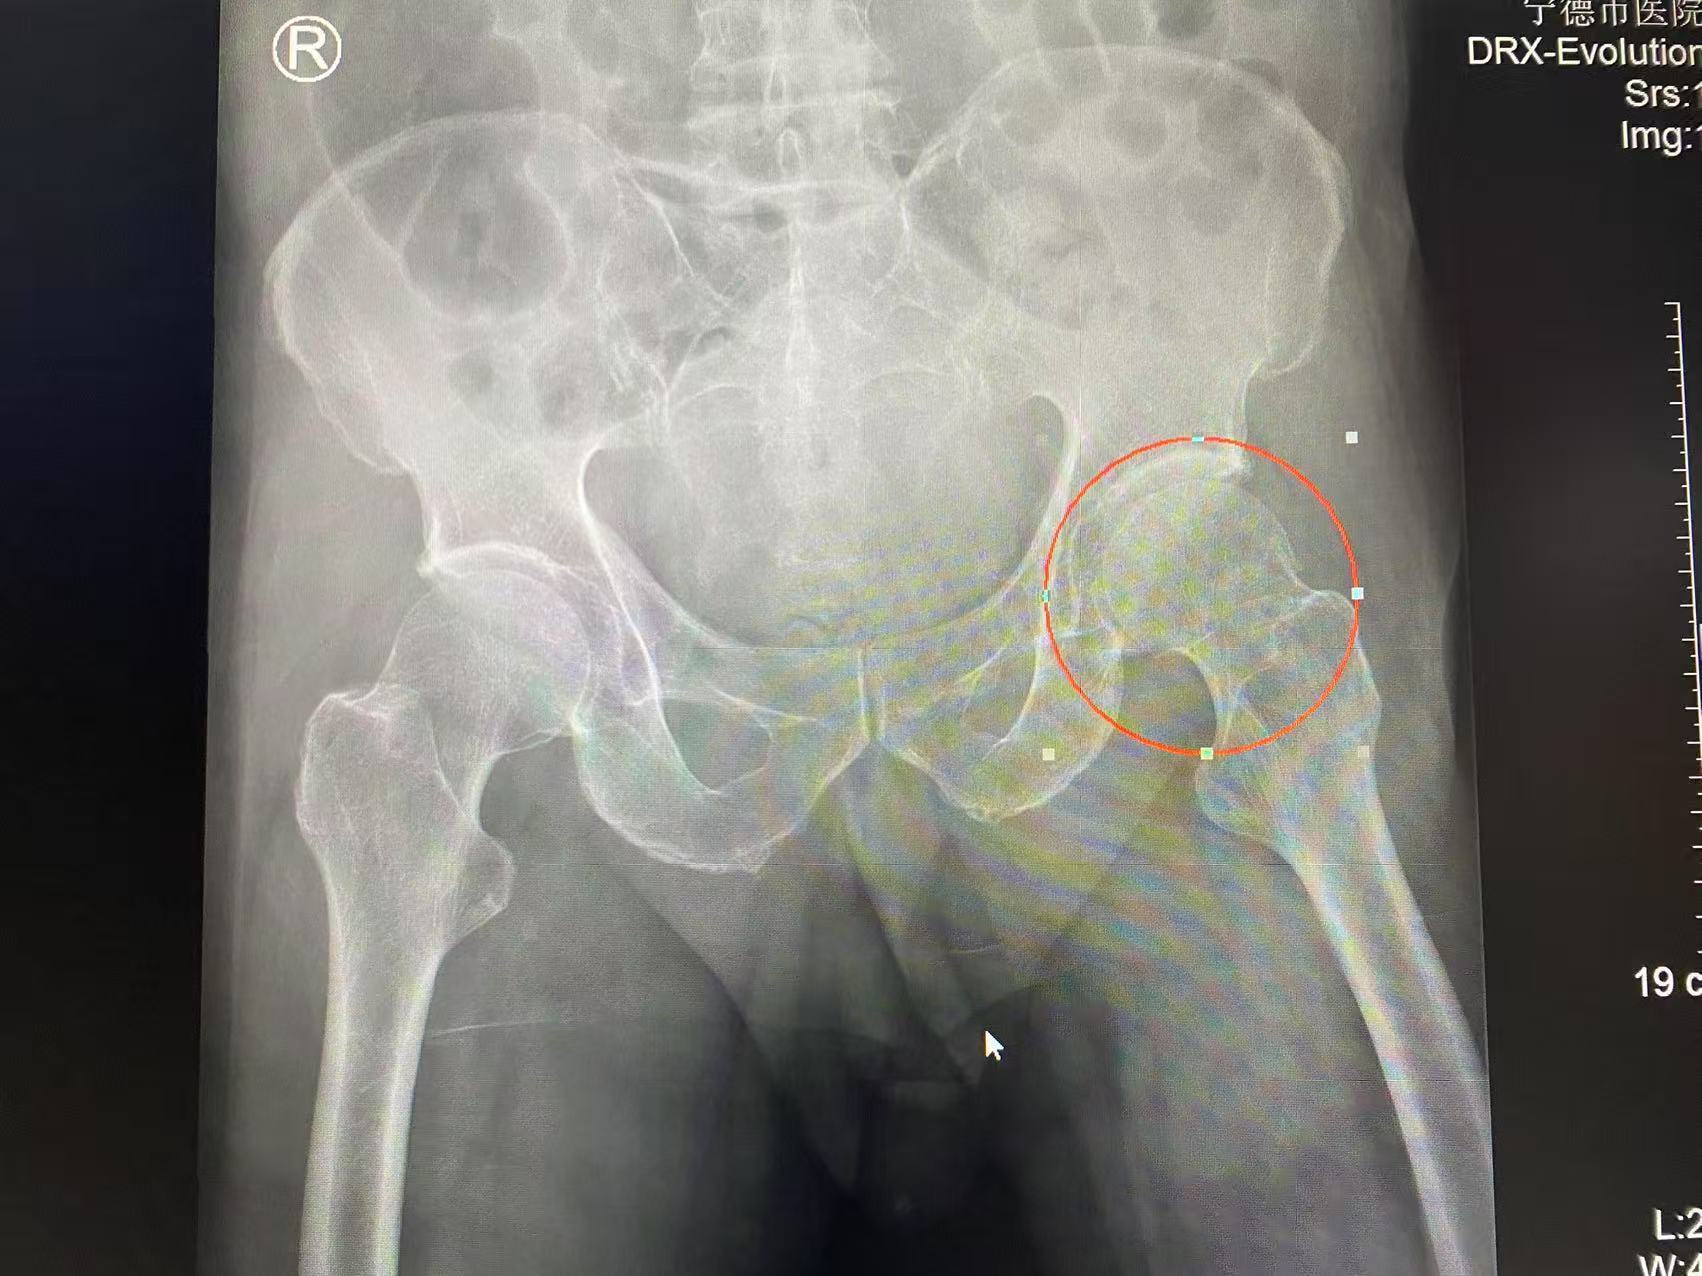

93岁高龄的张大爷(化名)在家不慎跌倒后,辗转来到宁德市医院。宁德市医院关节与运动医学科与上海市第一人民医院陈疾杵名医工作室联动,远程会诊,制定入院后快速诊疗流程。关节与运动医学科主任医师林久灶、柯铭锋及副主任医师董乃健医疗组迅速响应,即刻启动老年髋部骨折绿色通道,快速完成包括心电图、血生化、肺部CT、心脏彩超等在内的各项检查。考虑到老人本身有岁合并冠心病、心脏支架植入等基础疾病,在报告结果出来后24小时内邀请心内科、麻醉科专家迅速全面评估,进行术前多学科会诊,为患者制定个性化围手术期处理方案。

2月6日,林久灶医疗团队为张大爷实施人工股骨头置换及大粗隆骨折固定手术。术后第1天,老人即可床边坐起,在助行器辅助及家属搀扶下可下地行走;术后第4天,老人自己能下床用助行器行走。目前恢复顺利。